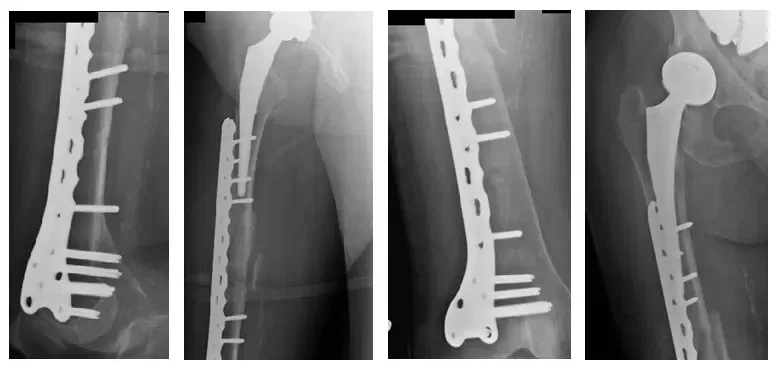

Dans la procédure ORIF, une plaque coulissante mini-invasive a été placée dans la fracture sans s’approcher du côté de la fracture.

Films peropératoires

Les images postopératoires montrent un ORIF fémoral droit